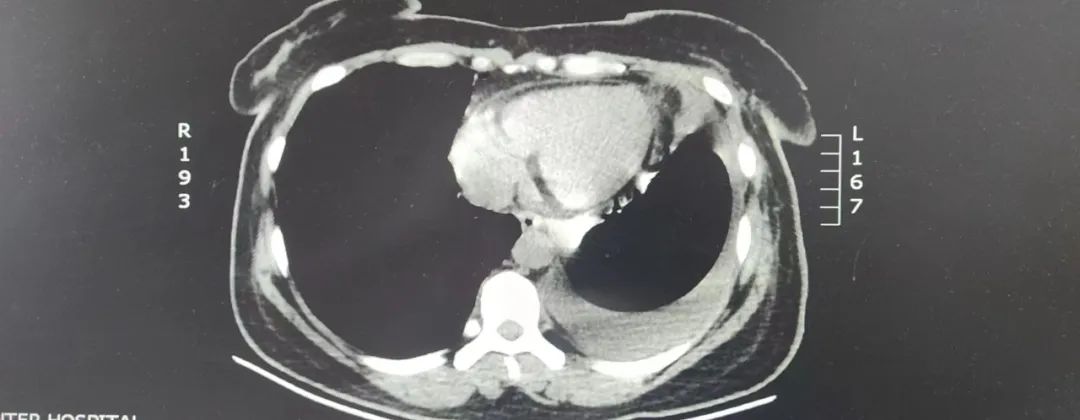

入住市中心医院胸外科后,胸CT检查示纵膈内心包左侧见团状脂肪密度影,较大层面大小约9.7*14.2厘米。完善纵隔磁共振等相关检查,根据检查结果高度怀疑纵膈内脂肪肉瘤。

考虑该区域内有心脏及大血管、神经等器官、组织,如果任其发展,最后将会导致这些重要器官、组织受压或者受侵犯,甚至危及生命,手术切除是此类疾病最有效的治疗方法。